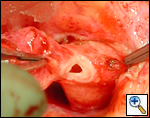

The operative approach is through a median sternotomy with the use of cardiopulmonary bypass and bicaval venous cannulation. The first dose of cold blood cardioplegia is antegrade; the remaining doses are retrograde.

High ascending aortic cannulation adjacent to the innominate artery for maximum exposure of the ascending aorta and to allow length for positioning of the patch in the ascending aorta.

One dose of antegrade cardioplegia followed by retrograde cardioplegia.

Pulmonary homograft or pericardial patches (tanned in glutaraldehyde) for the “shields”. These patches should not be too large – this will lead to aortic insufficiency.

First coronary sinus incision in noncoronary sinus to facilitate exposure of the incisions into the coronary orifice sinuses.

In most cases, the right coronary artery sinus should be opened to the left of the coronary orifice and the left coronary artery sinus to the right of the coronary orifice. Occasionally one may not have enough room between a coronary orifice and the aortic valve; in this case the incision site should be tailored to the situation.

Ensure similar orifice sizes between the proximal and distal ascending aorta after patch augmentation by the use of a sizing dilator.

Transesophageal echocardiography to assess completeness of repair, coronary blood flow postoperatively, wall motion abnormalities, and adequacy of aortic valve.